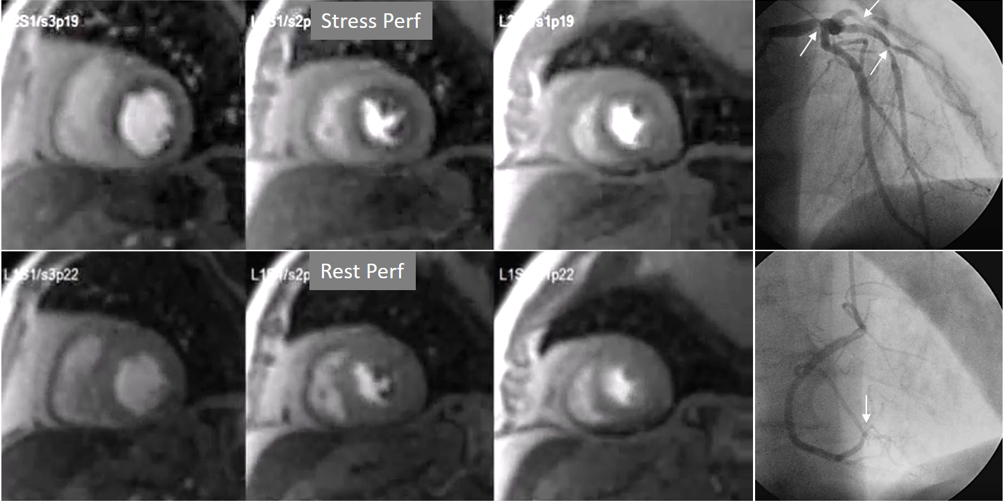

Perfusion defects in different territories can be detected in case of multivessel disease (Fig. 7) and, in patients with severe 3-vessel CAD, the perfusion study may show a global, intense, persistent defect which is readily recognizable (Fig. 8).

Fig. 7.Two-vessel perfusion defect. Stress perfusion defects at the anterior (white arrows) and inferior (black arrows) walls, not present at rest. Angiography (right panels) shows significant stenoses (white arrows) of the LAD (upper panel) and the right coronary artery (RCA) (lower panel).